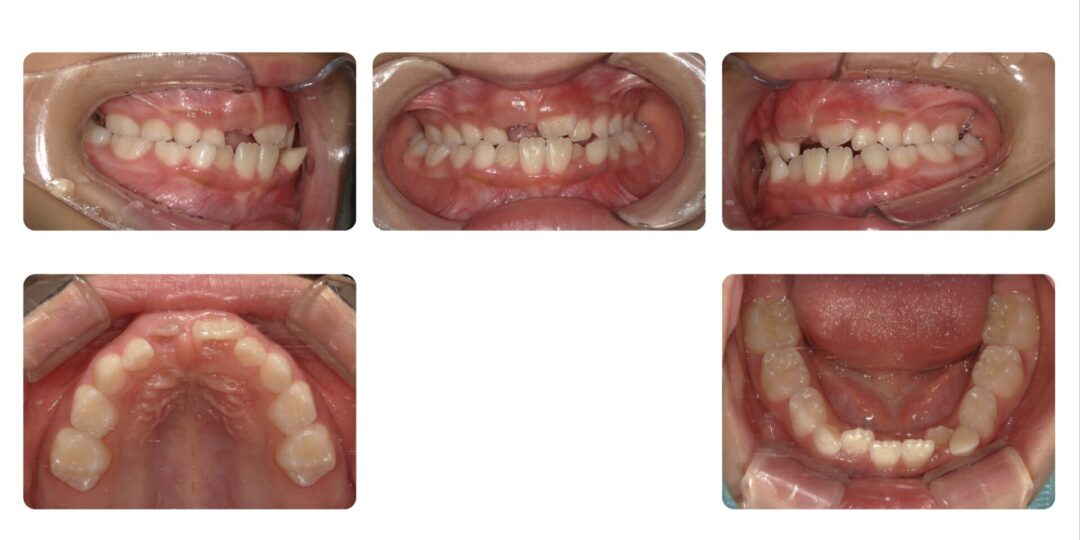

矯正治療後

3年2ヶ月

自由診療 基本料金¥330,000 処置料¥3,300